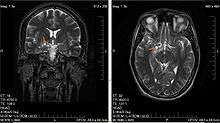

| Glioma in the left parietal lobe (brain CT scan), WHO grade 2. | |